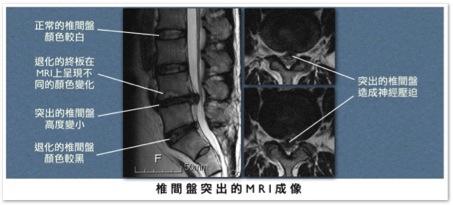

X光照相除了可能看到椎間距離減小或輕微的脊椎退化之外,因看不到椎間盤,並不能作為確診的依據。電腦斷層掃描

(computed tomography, CT) 或核磁共振造影 (magnetic resonance

imaging, MRI)

才可清楚看到突出的椎間盤,並評估神經根受壓迫的程度。兩種檢查各有優缺點,孰優孰劣在文獻上尚未有定論,雖然各國學者都同意能同時有兩種檢查的影像分析是最好的選擇(美、日、韓等國都是如此),但在本國有礙於中央健保局的規範,兩者只能擇一進行;本人較偏好核磁共振造影,因其對脊椎內腫瘤、膿瘍等嚴重疾病的鑑別率遠較電腦斷層高。